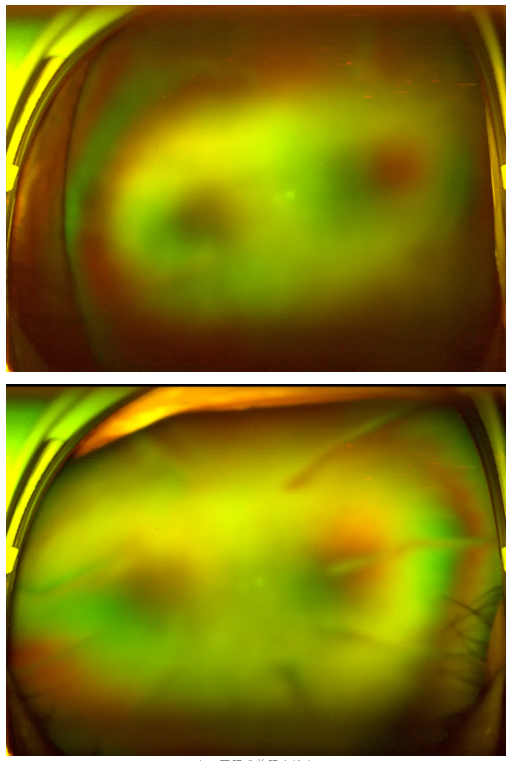

作為深耕眼科領(lǐng)域20余年的專家,王曉波主任擅長復(fù)雜糖尿病視網(wǎng)膜病變的診斷與治療,臨床經(jīng)驗極為豐富。接診后,他為老王進(jìn)行了全面細(xì)致的檢查,發(fā)現(xiàn)老王雙眼視力確實極差——右眼僅剩眼前指數(shù),左眼僅剩手動指數(shù),但眼底病變情況并未到無法挽救的程度;此外,他還合并有雙眼老年核性白內(nèi)障,這也是導(dǎo)致他進(jìn)一步加劇視力下降的原因之一。

老王雙眼術(shù)前眼底檢查